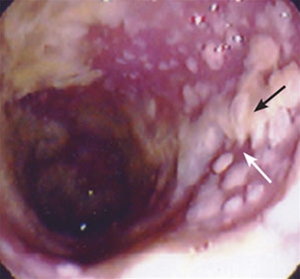

Pseudomembranøs kolit

• Endoskopi

• I særlige tilfælde kan CDI diagnosticeres ved endoskopisk/histopatologisk fund af pseudomembranøs colitis

• Viser gulgrå pletvise fibrinøse membraner (pseudomembraner), som dækker tarmvæggen ved de alvorligere tilfælde

• Lader sig let fjerne og giver punktvis blødning

• Kan være vanskelig at skelne fra anden kolitis, men biopsi kan vise typiske forandringer